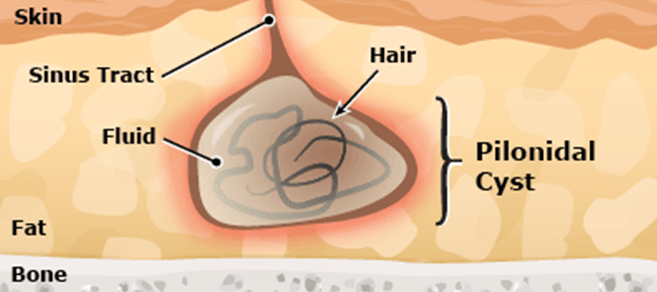

Causes

The cause of these cysts is not clear. They may form when a hair is forced under the skin or when a hair follicle ruptures. Or, a person may be born with the cyst.

Symptoms

A Pilonidal cyst does not cause symptoms unless it becomes infected. Infection may cause the following symptoms:

- Symptoms vary from a small dimple to a large painful mass

- One or more Pits are formed in the skin of gluteal fold

- Pits may be plugged with hair

- Abscess forms when drainage of pit is blocked.

- Pain, redness, and swelling of the cyst and area around it

- There may be a discharge that is clear, cloudy or bloody.

- Foul-smelling drainage from the cyst

- Fever